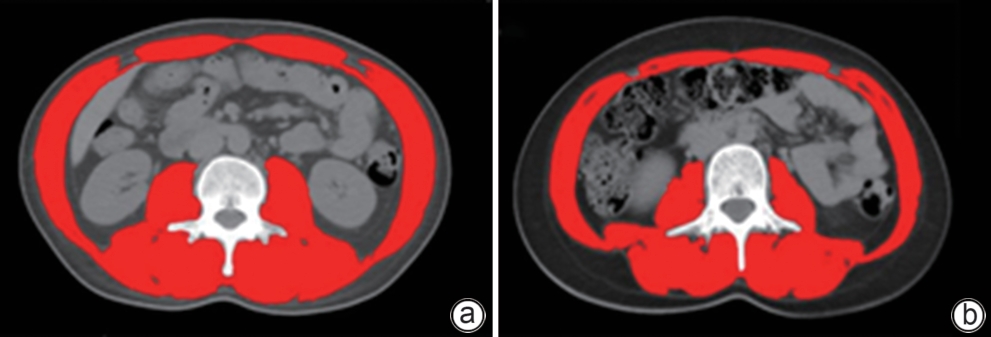

Establishment and validation of a risk prediction model for 90-day mortality in patients with acute-on-chronic liver failure based on sarcopenia

Huina CHEN, Ming KONG, Siqi ZHANG, Manman XU, Yu CHEN, Zhongping DUAN

2025, 41(6): 1135-1142. DOI: 10.12449/JCH250620

Abstract(1035) HTML (300) PDF (2616KB)(64)

Abstract:

Objective  To establish and validate a new prediction model for the risk of death in patients with acute-on-chronic liver failure (ACLF) based on sarcopenia and other clinical indicators, and to improve the accuracy of prognostic assessment for ACLF patients.  Methods  A total of 380 patients with ACLF who were admitted to Beijing YouAn Hospital, Capital Medical University, from January 2019 to January 2022 were enrolled, and they were divided into training group with 228 patients and testing group with 152 patients in a ratio of 6∶4 using the stratified random sampling method. For the training group, CT images were used to measure the cross-sectional area of the skeletal muscle at the third lumbar vertebra (L3), and L3 skeletal muscle index (L3-SMI) was calculated. Sarcopenia was diagnosed based on the previously established L3-SMI reference values for healthy adults in northern China. Univariate and multivariable Cox regression analyses were used to establish a sarcopenia-ACLF model which integrated sarcopenia and clinical risk factors, and a nomogram was developed for presentation. The area under the ROC curve (AUC) was used to assess the predictive performance of the model, the calibration curve was used to assess the degree of calibration, and a decision curve analysis was used to investigate the clinical application value of the model. The independent-samples t test or the Mann-Whitney U test was used for comparison of continuous data between two groups, and the chi-square test was used for comparison of categorical data between two groups. The Kaplan-Meier method was used to plot survival curves, and the Log-rank test was used for comparison between groups. The DeLong test was used for comparison of AUC between different models.  Results  The multivariate Cox regression analysis showed that sarcopenia (hazard ratio [HR]=1.962, 95% confidence interval [CI]: 1.185‍ ‍—‍ ‍3.250, P=0.009), total bilirubin (HR=1.003, 95%CI: 1.002‍ ‍—‍ ‍1.005, P<0.001), international normalized ratio (HR=1.997, 95%CI: 1.674‍ ‍—‍ ‍2.382, P<0.001), and lactic acid (HR=1.382, 95%CI: 1.170‍ ‍—‍ ‍1.632, P<0.001) were included in the sarcopenia-ACLF model. In the training cohort, the sarcopenia-ACLF model had a larger AUC than MELD-Na score in predicting 90-day mortality in patients with ACLF (0.80 vs 0.73, Z=1.97, P=0.049). In the test cohort, the sarcopenia-ACLF model had a significantly larger AUC than MELD score (0.79 vs 0.69, Z=2.70, P=0.007) and MELD-Na score (0.79 vs 0.68, Z=2.92, P=0.004). The calibration curve showed that the model had good calibration ability, with a relatively good consistency between the predicted risk of mortality and the observed results. The DCA results showed that within a reasonable range of threshold probabilities, the sarcopenia-ACLF model showed a greater net benefit than MELD and MELD-Na scores in both the training cohort and the test cohort.  Conclusion  The sarcopenia-ACLF model developed in this study provides a more accurate tool for predicting the risk of 90-day mortality in ACLF patients, which provides support for clinical decision-making and helps to optimize treatment strategies.